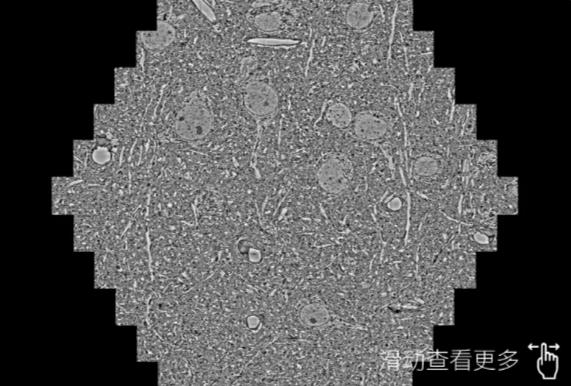

鼠脑切片。左图使用河西蔡司河西扫描电镜MultiSEM706对165μmx143pm面积区域成像,耗时仅需1.5秒。右图为鼠脑切片中30μm区域放大效果。样品由芝加哥大学B.Kasthuri提供。

使用蔡司高速河西扫描电镜MultiSEM对1mm²人脑皮层组织进行高分辨成像,并对其中的各种细胞结构进行三维重构分析。左图展示了2x3mm²组织平面中锥体神经元的三维重构效果。右图显示了局部体积神经元三维重构。图像由哈佛大学chtman实验室提供,渲染图由D. Berger 制作。